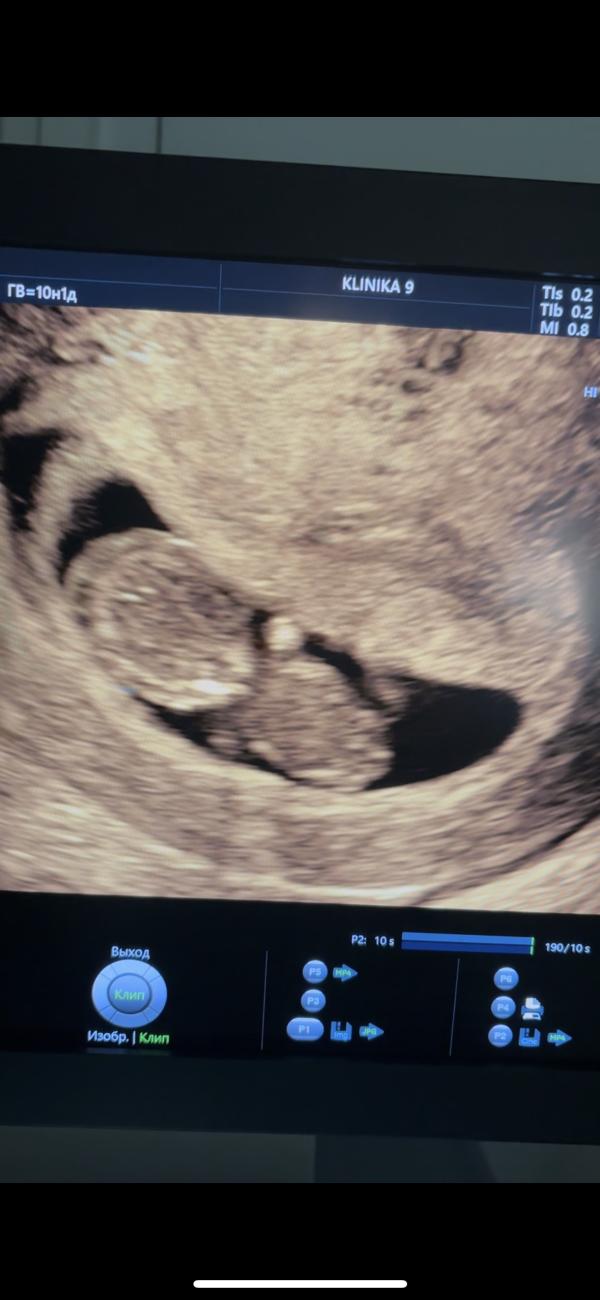

Сегодня была на узи🥰

Малыш(ка) очень не поседлев, и всё время двигался и переворачивался😍 (ни секунды спокойствия)

Акушерский срок 10,1, по ктр 9,5🙃 но ничего мы не переживаем👌🏼на последнем узи в 8,3 был тонус по задней стенке. Ставила по 1 свечке на ночь с папаверином 10 дней, но он до сих пор так и остался😒 теперь 1 утром и 1 вечером еще 10 дней(

КТР - 2,9 см

ПЯ -4,8 см

ЖМ - 5,8 мм

ЧСС - 174 уд/м